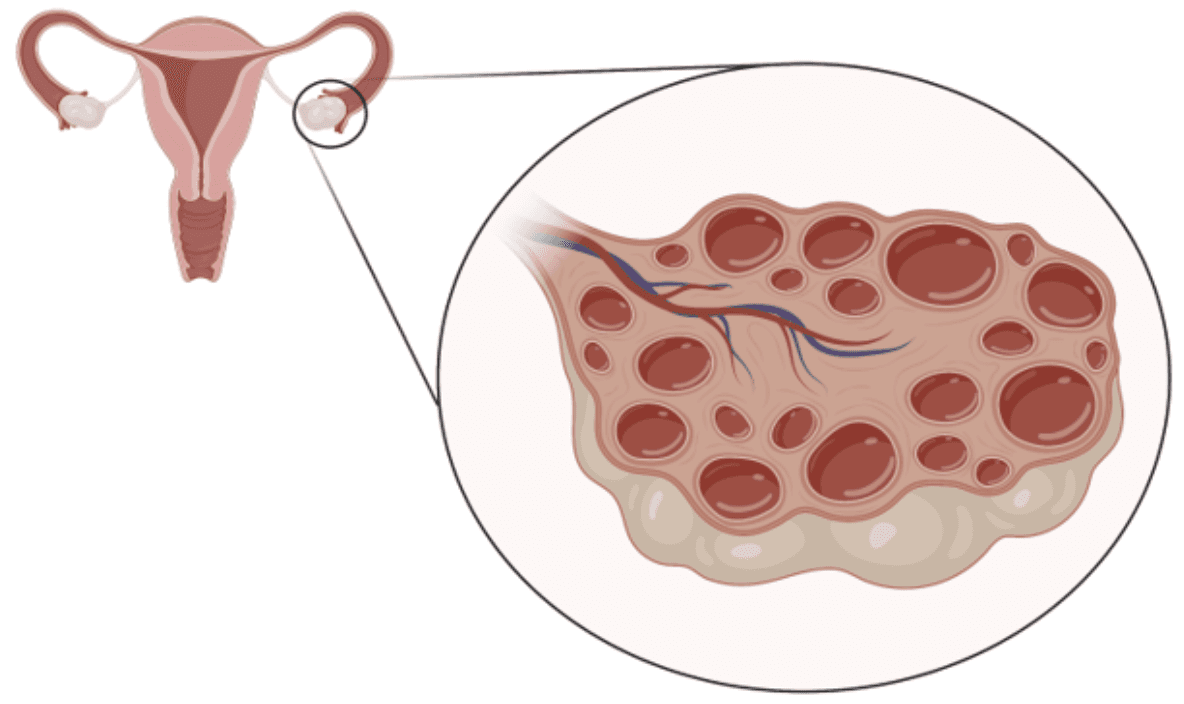

รังไข่มีถุงไข่ขนาดเล็กหลายๆใบจากอัลตราซาวด์

5️⃣ อัลตราซาวด์พบถุงไข่หลายใบ

รังไข่จะมีลักษณะถุงไข่เล็ก ๆ หลายใบเรียงรอบขอบรังไข่